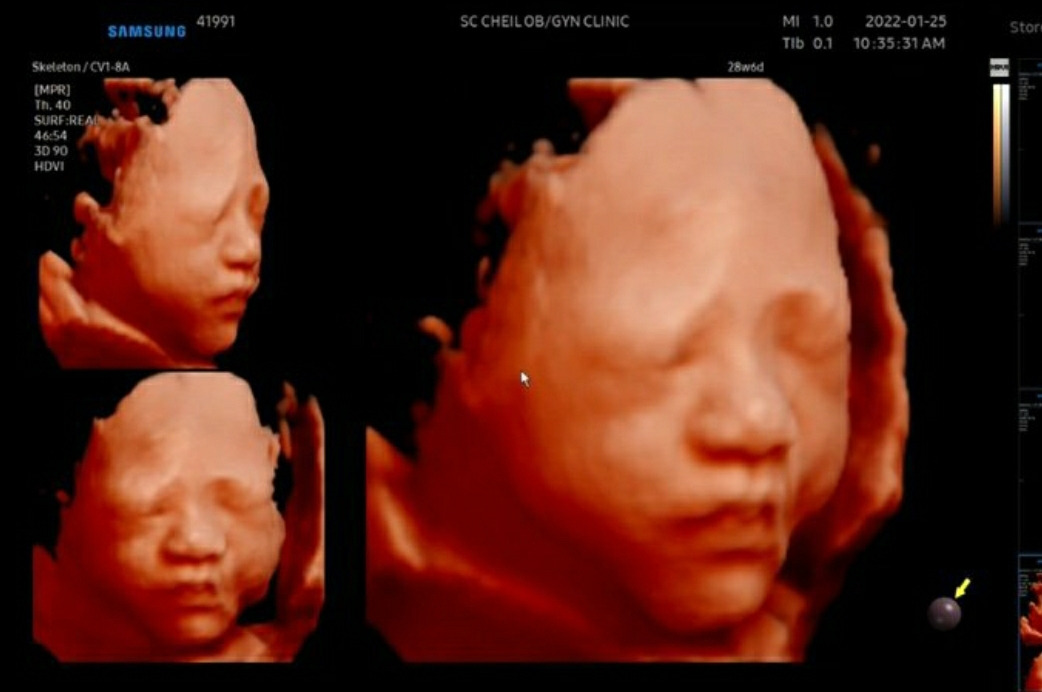

아가 초음파 사진

10달 동안 엄마 뱃속에서 엄마 배가 점점 커지는 걸 보며, 아가도 같이 크고 있다는 걸 느꼈어.

예정일이 있고, 다가오면서 아가가 나올 때쯤 되었을 때 긴장했던 기억이 난다. 아가가 너무 커서 나오면 출산할 때 힘들고, 너무 작을 때 나오면 조산이라서 적당한 때 나오길 기다렸었어.

다행히 아가는 엄마 뱃속에서 잘 있어서, 너무 늦게 나오는 것만 걱정하면 됐었어.